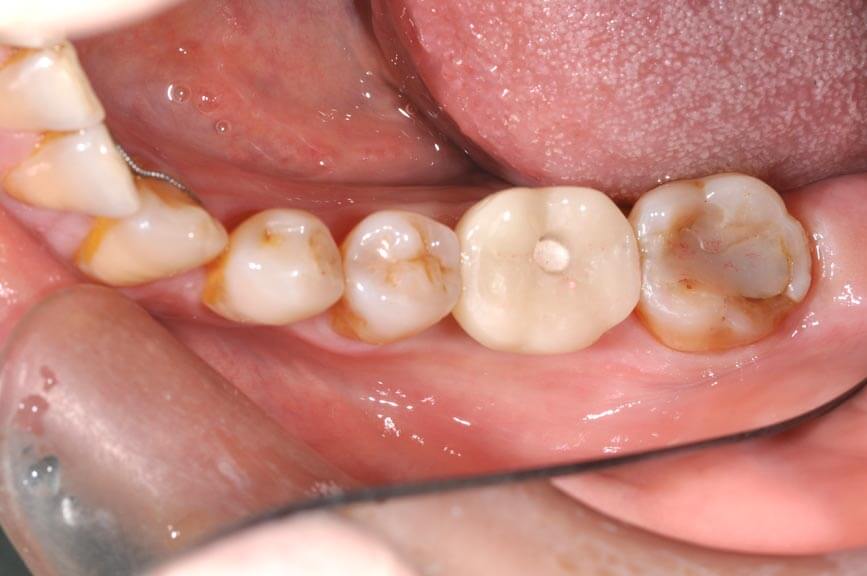

植牙前

植牙全瓷牙冠

植牙後

更多植牙案例